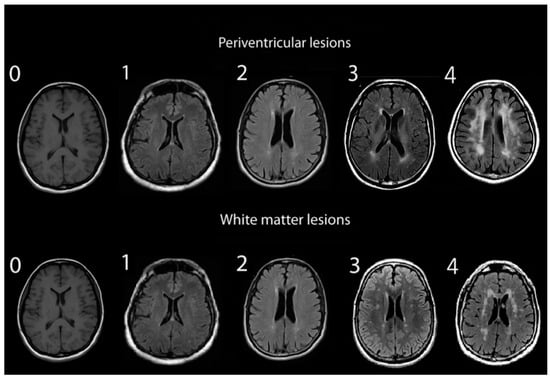

2.2. Assessment of White Matter Hyperintensities